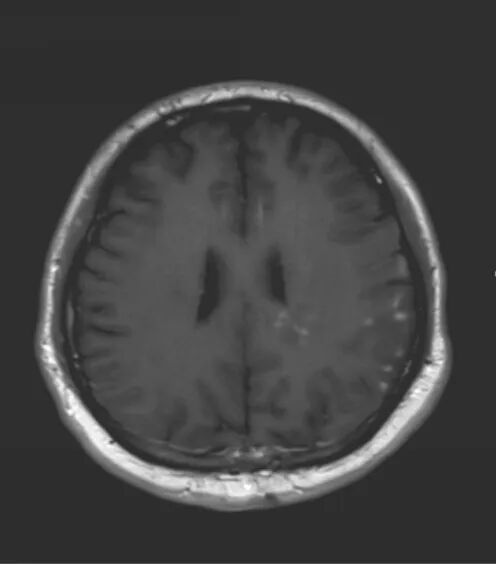

医生要求紧急做颅脑MRI,影像很快就传到了电脑上(图1-6)。医生解释,小脑蚓部占位考虑“脂肪瘤”,另有侧脑室旁白质脱髓鞘和左侧额顶叶皮质性脑炎的改变,“癫痫”可能为“继发性癫痫”。

图5 侧脑室旁病变T2